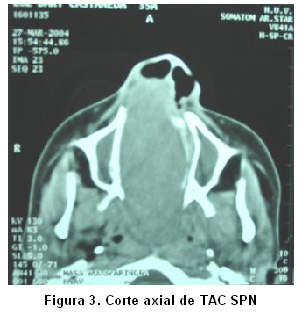

Se tomó una escanografía de SPN que informó la presencia de una masa en la fosa nasal derecha, con densidad de tejidos blandos que desplazaba el septo nasal hacia el lado izquierdo, y ocluía completamente la vía aérea nasal. En la ventana ósea se encontró que las paredes del antro maxilar estaban adelgazadas y desplazadas. La vía área a nivel de la rinofaringe se encontró ocluida en 80% (Fotos 2 y 3).